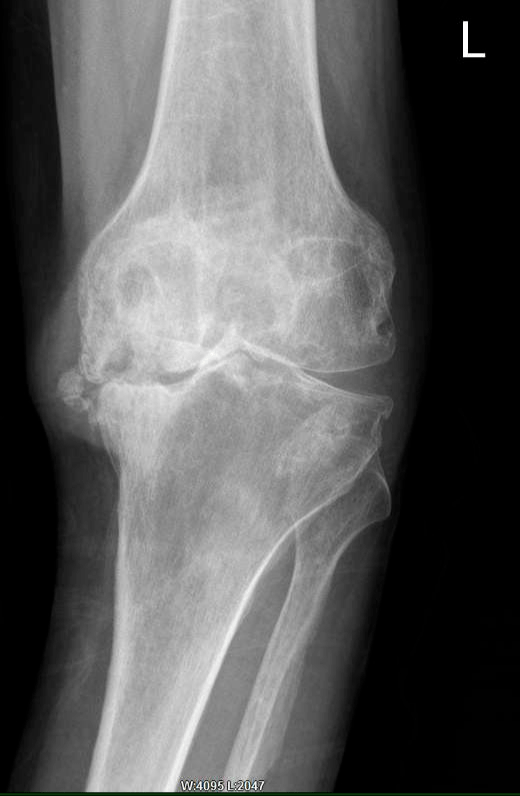

青岛海慈医院王相利 你的膝关节炎适合做膝关节置换手术吗

阿勒泰地区人民医院独立自主完成首例复杂全膝关节置换术